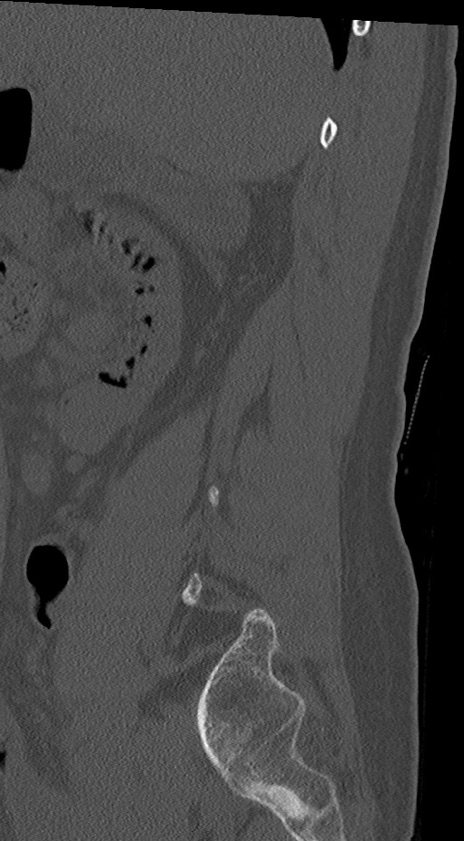

【整形】TIPS症例4 腰椎CT(矢状断像)

腰椎CT

冠状断像